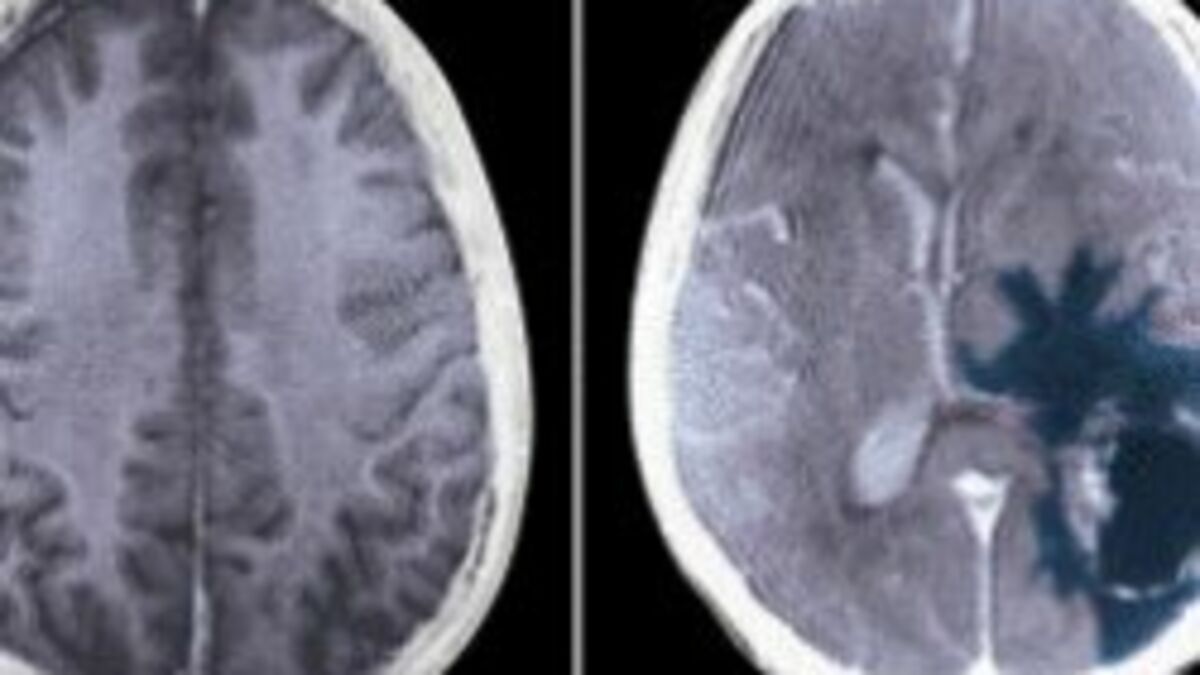

Kanada’nın Montreal kentinde yaşayan Andreea Vanacker isimli bir kadına, yüzünün belirli bir tarafında duyduğu ağrıların sebebinin 10 yıldır sessizce büyüyen bir beyin tümörü olduğu söylendi.

Doktorlar, ağrının kafatasının içindeki büyük, iyi huylu bir tümörün yüz kaslarını kontrol etmekten sorumlu sinire baskı yapmasından kaynaklandığını söylerken Vanacker, yaşadığı ağrının bir sabah uyarı vermeden ortaya çıktığını ve konuşmaya, gülmeye hatta yemek yemeye çalıştığında da ortaya çıktığını söyledi.

Tümör, doktorların kafatasının bir kısmını çıkarmak ve beyni kesmek zorunda kaldığı bir ameliyatla alındı. Tümörün tümü çıkartıldı ancak Vanacker gücünü geri kazanmasının bir yıl sürdüğünü söyledi.